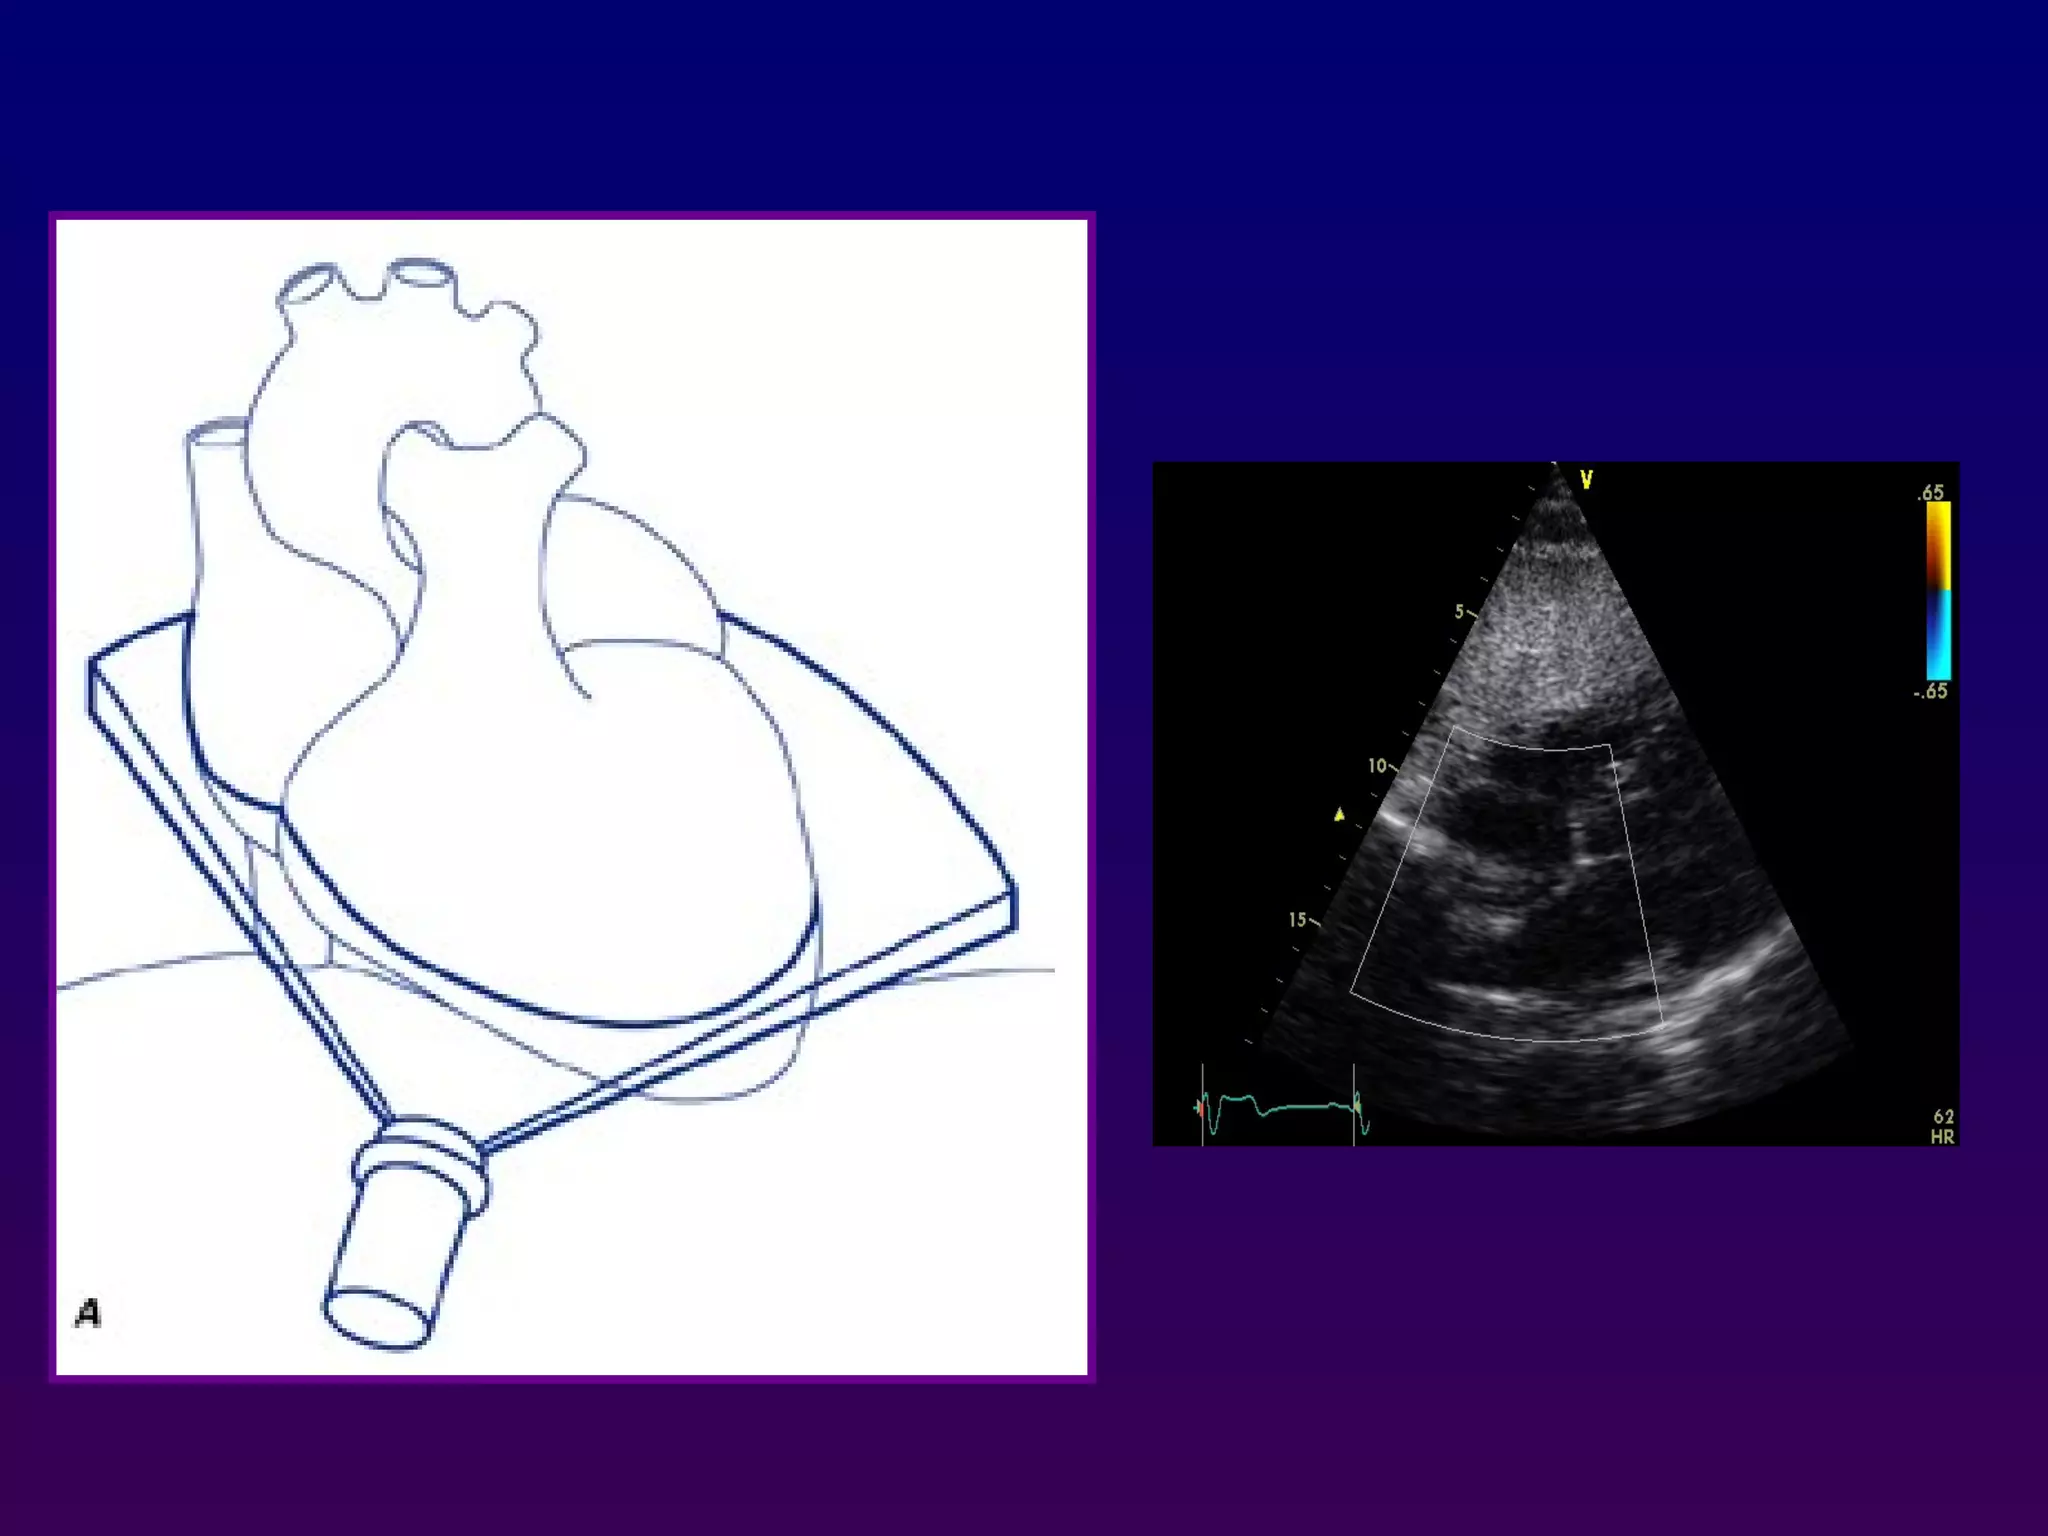

Parasternal long axis

With the transducer in the 3rd or 4th right intercostal

space immediately adjacent to the sternum and

patient in left lateral decubitus a long-axis view of

the heart is obtained which bisects the aortic and

mitral valve, Proper positioning of the probe results

in the ascending aorta being relatively horizontal in

orientation.

Parasternal long axis Withthe transducer in the 3rd or 4th right intercostal space immediately adjacent to the sternum and patient in left lateral decubitus a long-axis view of the heart is obtained which bisects the aortic and mitral valve, Proper positioning of the probe results in the ascending aorta being relatively horizontal in orientation. Lower intercostal positions may be necessary in patients with vertically oriented hearts due to chronic obstructive pulmonary disease.